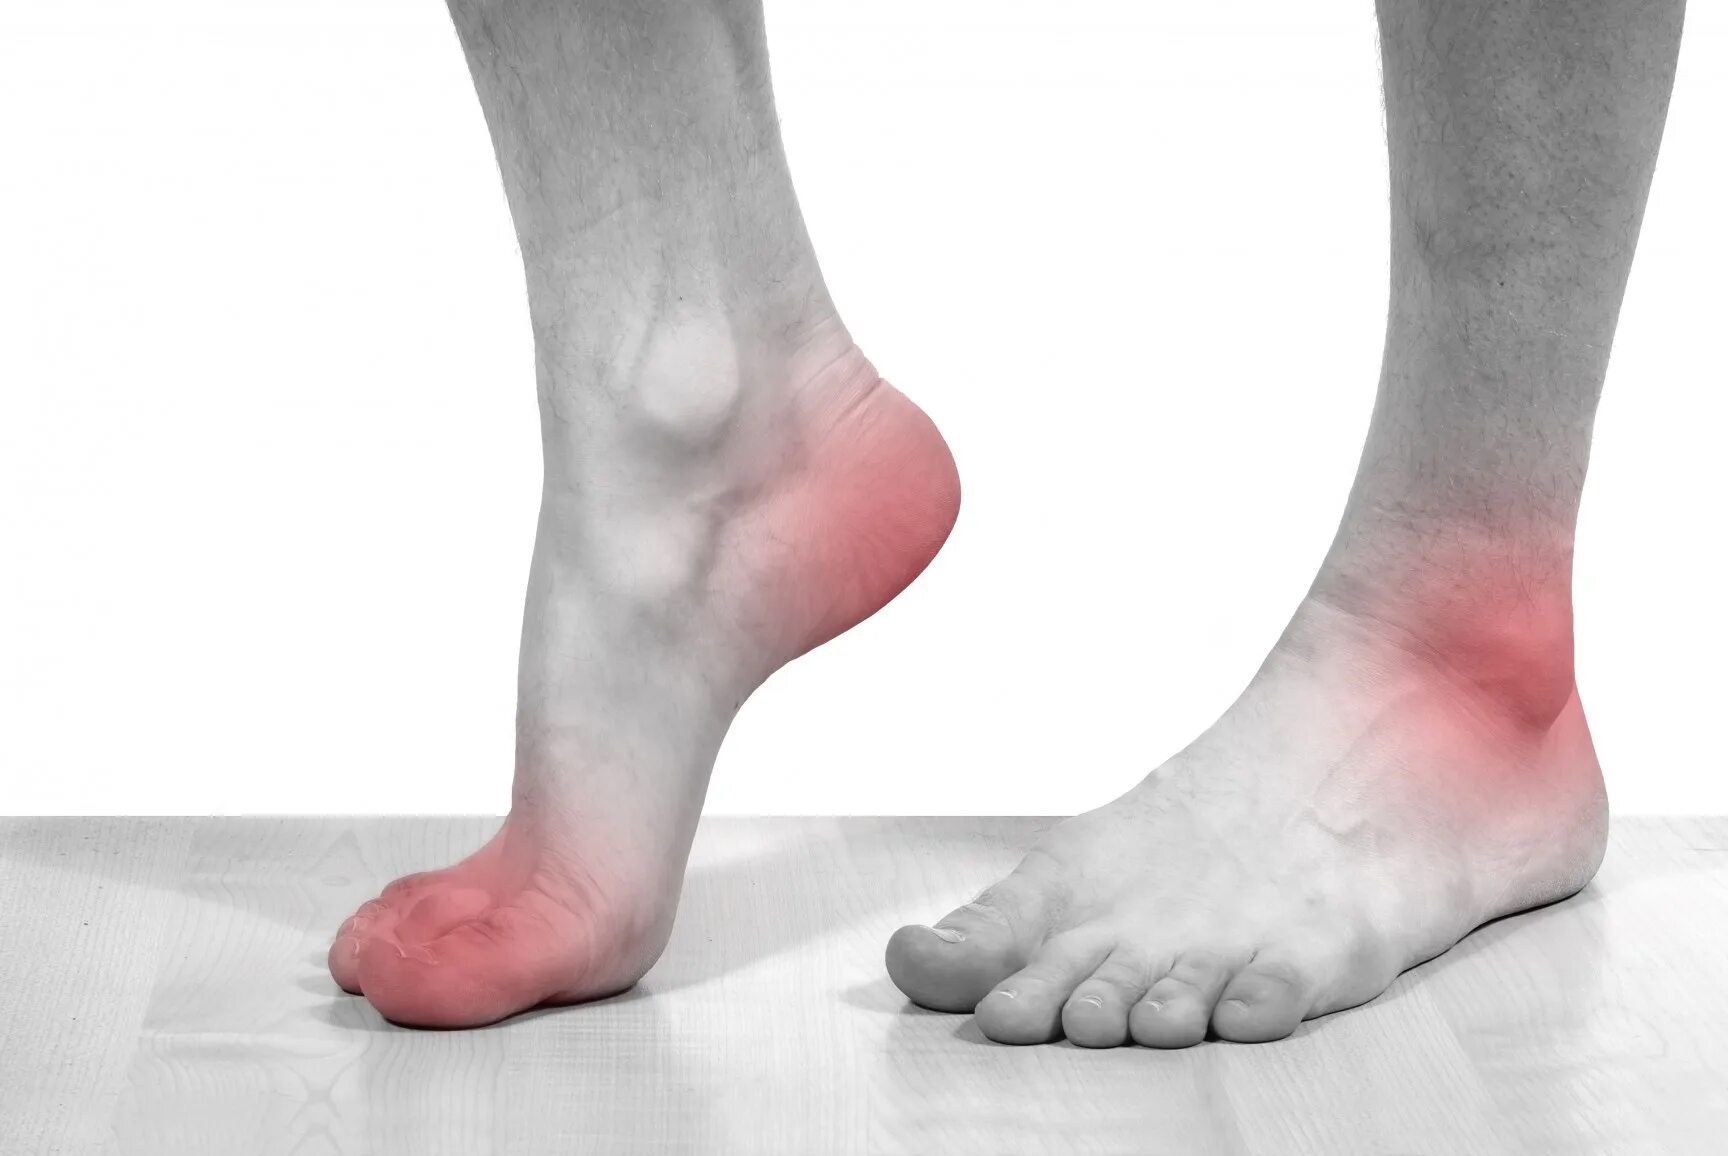

Артроз пяточных суставов